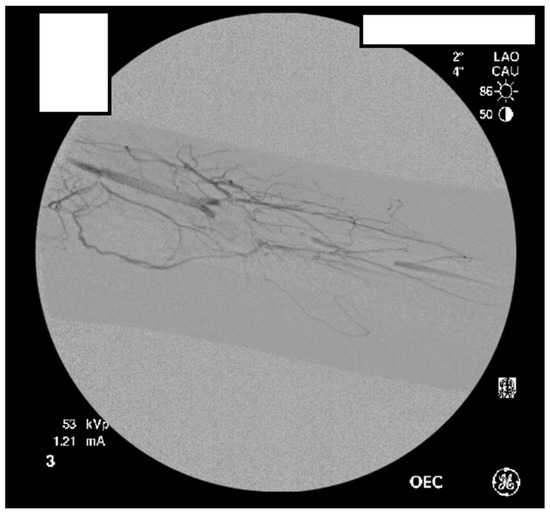

A heparin drip was then initiated, and she was taken to the catheterization lab for thrombolysis. This was carried out with Alteplase for 48 h as the patient had strong collaterals and was not in limb-threat (Figure 7, Figure 8, Figure 9, Figure 10 and Figure 11). However, her radial artery remained occluded. She was then taken to the operating room for thromboembolectomy of the left brachial and radial arteries (Figure 12). She was continued on anticoagulation post-operatively and was discharged.

Figure 7.

Left subclavian arteriography demonstrating a thrombosed brachial artery at the mid-humeral level and extensive collateralization proximally.

Figure 8.

Left subclavian arteriography in an ATOS patient in stress position demonstrating a totally occluded subclavian artery.

Figure 9.

Distal left arm angiography in an ATOS patient demonstrating an occluded radial artery at the origin and ulnar artery at the mid-forearm.

Figure 10.

Angiography of the radial and ulnar arteries as well as the palmar arch and digital branches in an ATOS patient with a brachial thrombus.

Figure 11.

Distal brachial artery thrombosis in an ATOS patient.